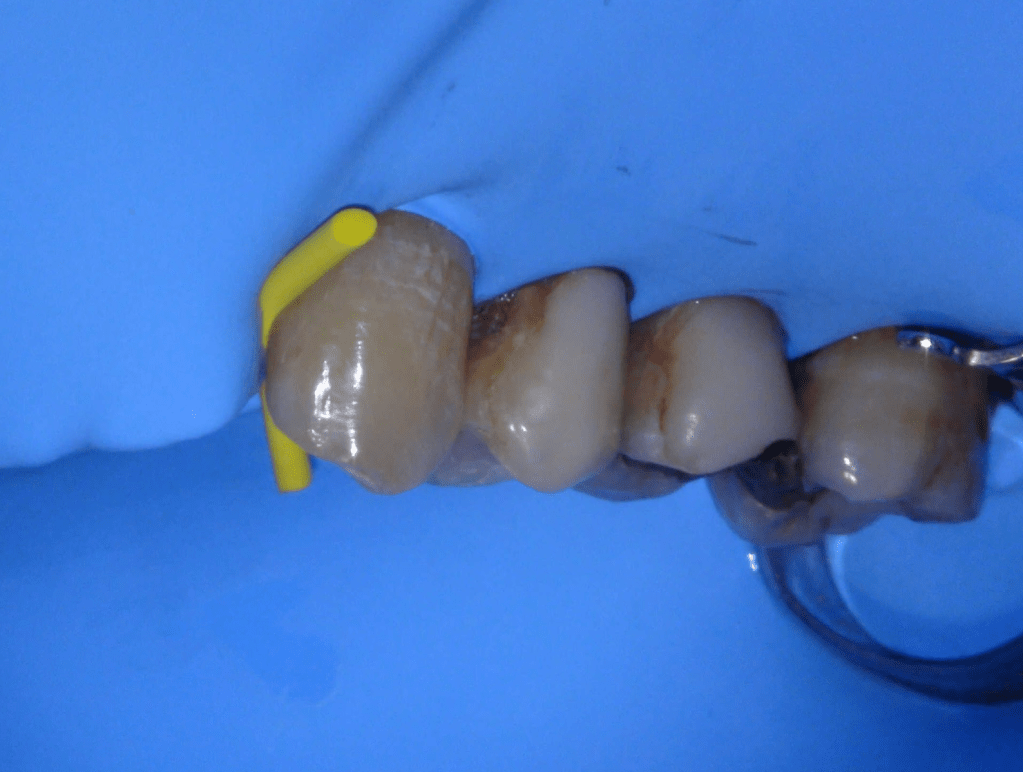

Diagnóstico de fisuras y fracturas

Diente fisurado regeneración total

Diente fisurado tratable

Diente fisurado tratable con endodoncia

Diente fisurado tratable endodoncia 2

Fisura, remoción amalgama para explorar

Fractura cuspídea tratable

Vertical root fracture